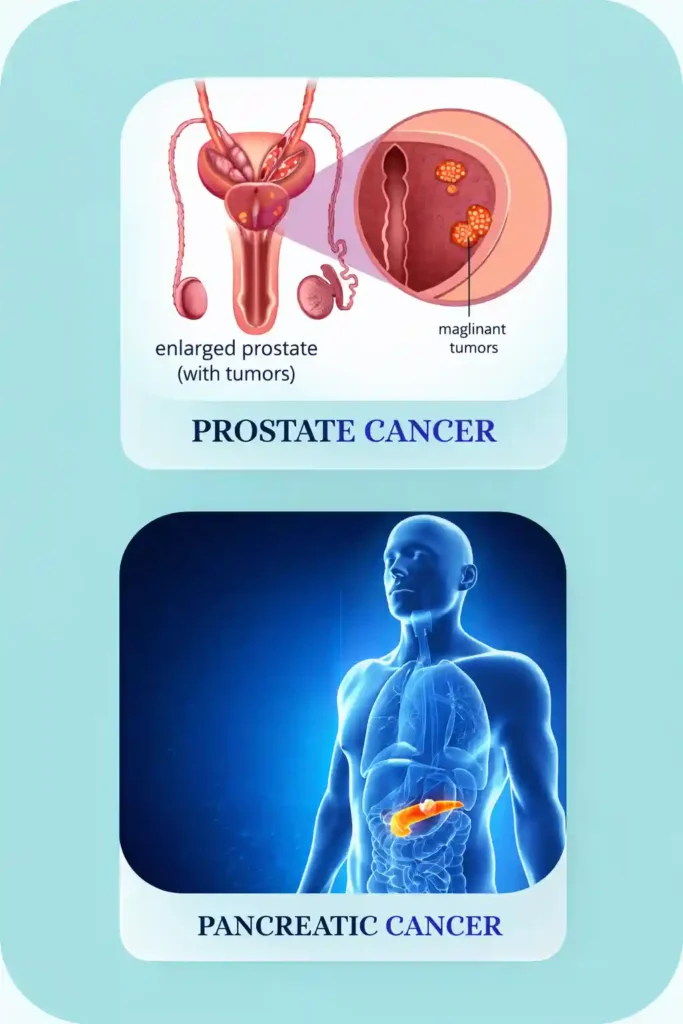

- Supports tissue healing after surgery

- Helps improve urinary comfort

- Strengthens immune response

- Reduces treatment-related inflammation

- Supports overall vitality

- Supports tissue healing after surgery

- Helps improve urinary comfort

- Strengthens immune response

- Reduces treatment-related inflammation

- Supports overall vitality